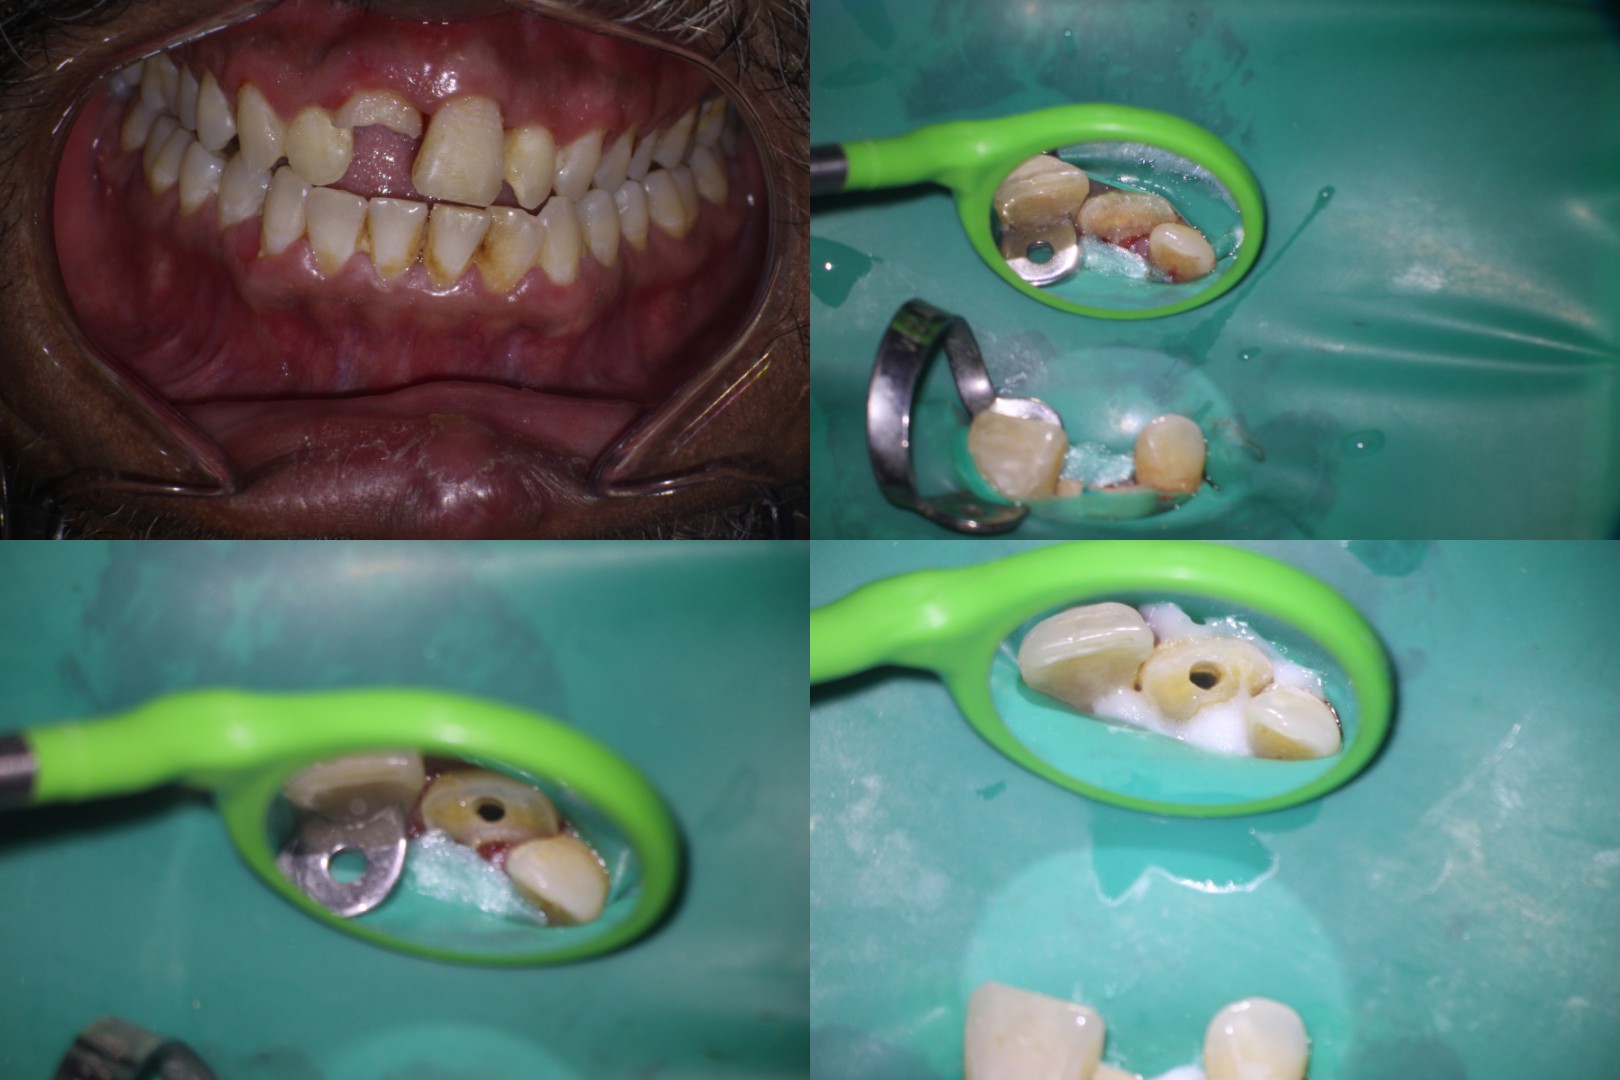

Pt 47 yoM reported after 10 days of trauma to his front teeth. Clinical examination revealed crown fracture of #8 with pulp exposure. #9 and #10 were normal to cold test. Periapical radiograph showed intrusion of #8. Root canal therapy was started and obturation completed after 2 sittings of CAOH. FRC post luted and composite build up done.